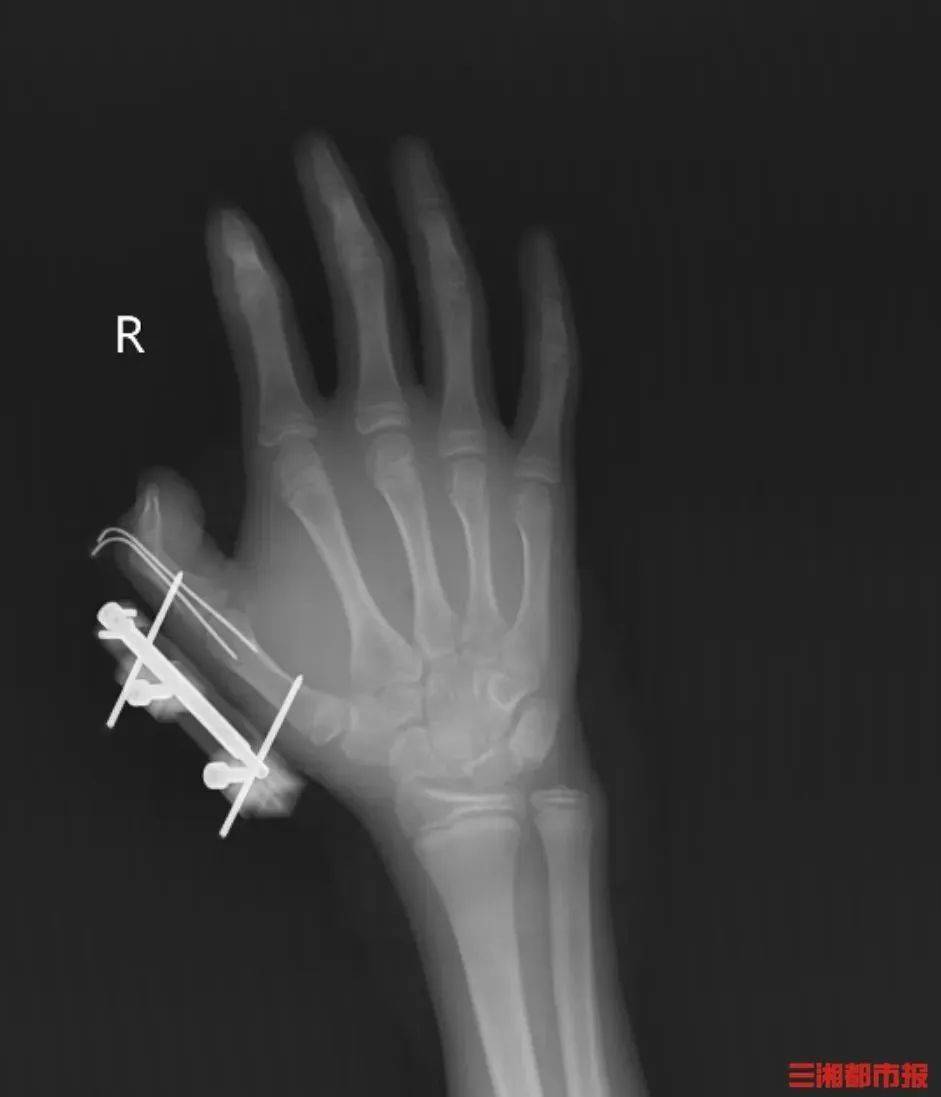

冰镇冷饮冰淇淋 为冷链食物保鲜 干冰在日常生活中十分常见 但很多人不知道 干冰若储存、使用不当 便会“暗藏杀机” 把干冰当玩具摇 14岁少年手指被炸得深可见骨...